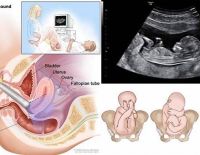

• Siêu âm

Siêu âm 3D là kĩ thuật siêu âm y khoa, sử dụng chủ yếu để chẩn đoán thai nhi, tim, hậu môn - trực tràng, mạch máu. Hiện nay, nhắc tới siêu âm, siêu âm 3D được người ta nói đến rất nhiều. Vậy nó...

Thai 12 tuần siêu âm bụng hay đầu dò sẽ tốt cho thai nhi?

Thai 12 tuần siêu âm bụng hay đầu dò là vấn đề rất nhiều mẹ mang thai không biết. Việc chọn hình thức siêu âm trong từng giai đoạn đóng vai trò rất quan trọng trong quá trình khám thai. Vậy thai 12 tuần siêu...

Siêu âm 2D – Những thông tin mẹ bầu nên nắm bắt kịp thời

Siêu âm 2D là hình thức siêu âm dành cho các mẹ bầu ở những tuần đầu của thai kỳ. Đây là phương pháp siêu âm cũ nhưng vẫn được áp dụng nhiều hiện nay. Khi siêu âm 2D các mẹ bầu vẫn nắm được...